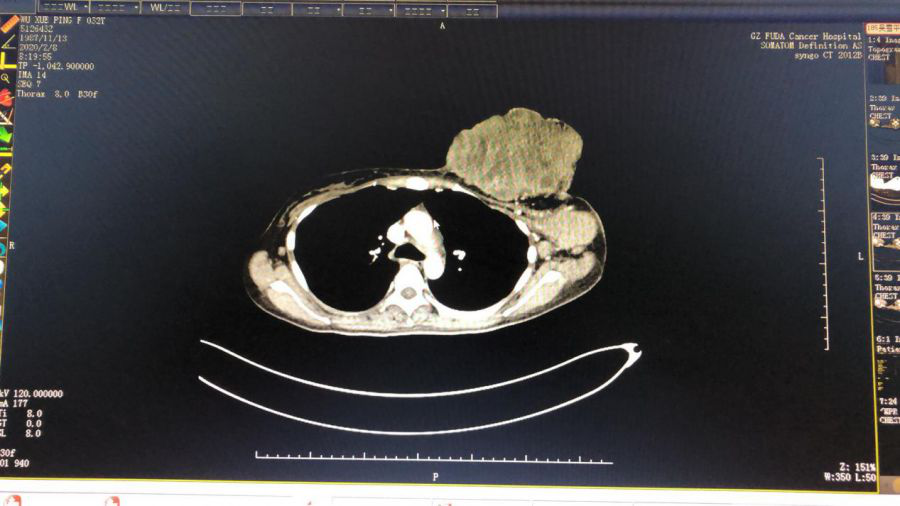

02 团队的力量 使治疗效果达到事半功倍

2月8日,星期六,放射科医护人员主动放弃休假时间赶回医院为帮助李梅进行一系列超声及CT检查,报告显示:软组织肿块呈现形态不规则,大小约17.1×8.1×18.9cm,双侧腋窝、左侧锁骨下区及纵膈内可见多个肿大及稍大淋巴结,左侧腋窝较大者约6.3×4.4×5.6cm,双肺多发转移瘤,较大位于右肺中叶,大小约2.3×2.7cm。